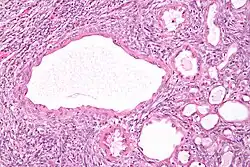

| Micrograph of a cystic nephroma (left of image). Normal kidney is seen on the right. H&E stain. | |

A cystic nephroma, also known as multilocular cystic nephroma, mixed epithelial stromal tumour (MEST) and renal epithelial stromal tumour (REST),[1] is a type of rare benign kidney tumour.

Cystic nephromas are diagnosed by biopsy or excision. It is important to correctly diagnose them as, radiologically, they may mimic the appearance of a renal cell carcinoma that is cystic.[2]

Pathologic diagnosis

The characteristics of cystic nephromas are:

- Cysts lined by a simple epithelium with a hobnail morphology, i.e. the nuclei of the cyst lining epithelium bulges into the lumen of the cysts,

- Ovarian-like stroma that has a:

- Spindle cell morphology, and has a

- Basophilic cytoplasm.